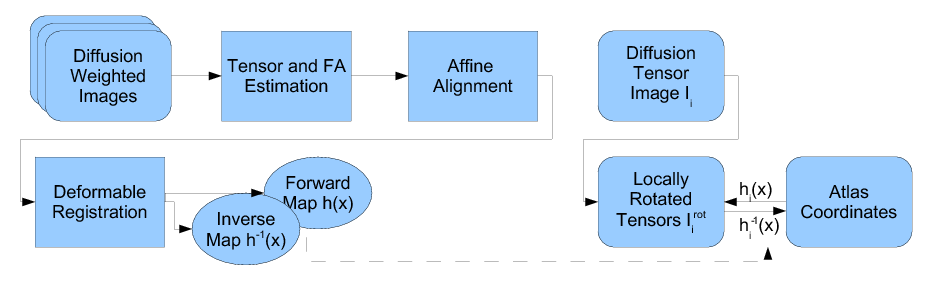

Our methodology for population analysis of DT-MRI is based on unbiased non-rigid registration of a population to a common coordinate system. The registration jointly produces an average DTI atlas, which is unbiased with respect to the choice of a template image, along with diffeomorphic correspondence between each image. The registration image match metric uses a feature detector for thin fiber structures of white matter, and interpolation and averaging of diffusion tensors use the Riemannian symmetric space framework. The anatomically significant correspondence provides a basis for comparison of tensor features and fiber tract geometry in clinical studies.